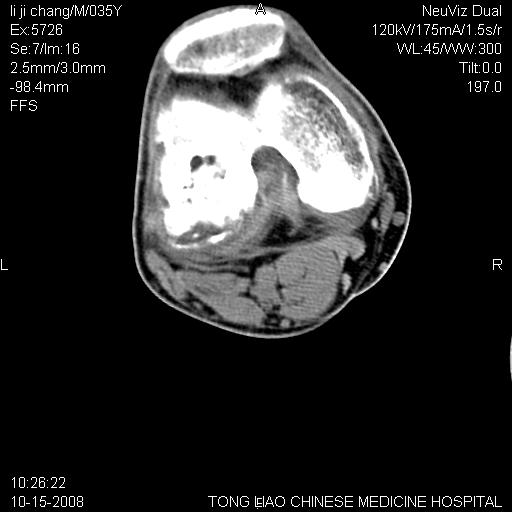

男,35岁,骨科诊断骨性关节炎。继往使用过激素,现股骨头坏死。膝关节病变,请会诊

一元论-----亦考虑为坏死

支持考虑无菌坏死

支持无菌坏死伴退行性骨关节病.

剥脱性骨软骨炎:是一种关节下软骨及软骨下骨缺血性坏死。

支持 无菌性坏死伴退行性骨关节病。

支持无菌坏死伴退行性骨关节病